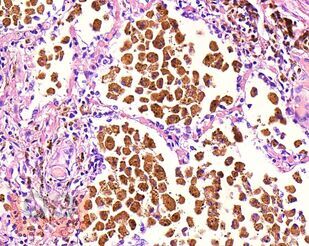

В учебном пособии представлен теоретический материал, перечень макропрепаратов и микропрепаратов, демонстрирующих типовые проявления патологических процессов. В цветных иллюстрациях и в описании микропрепаратов сделан акцент на наиболее важных гистологических изменениях, позволяющих на светооптическом уровне диагностировать и дифференцировать состояния, отклоняющиеся от нормы, в том числе с использованием различных гистологических окрасок. Пособие помогает выделить главные аспекты изучаемых патологических процессов, организовать и конкретизировать учебный процесс.